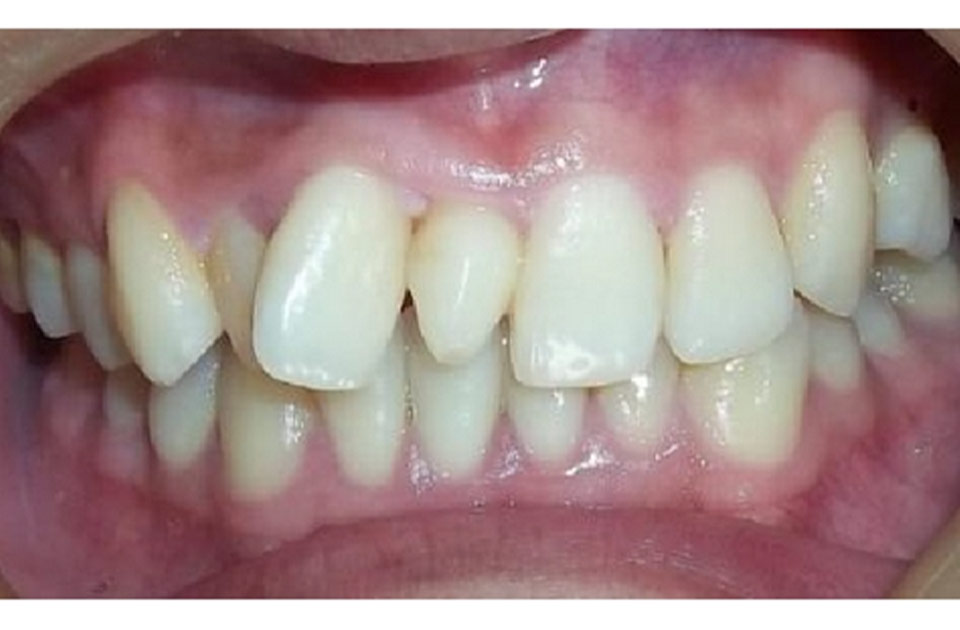

- عدم توازن در دندانها: این وضعیت ممکن است باعث بروز مشکلات زیبایی و عدم توازن در دندانها گردد.

برای اصلاح موقعیت دندانها و بهبود توازن فک، درمانهای ارتودنسی ممکن است لازم باشد. این درمان میتواند شامل استفاده از بریسها یا سایر وسایل ارتودنسی باشد.